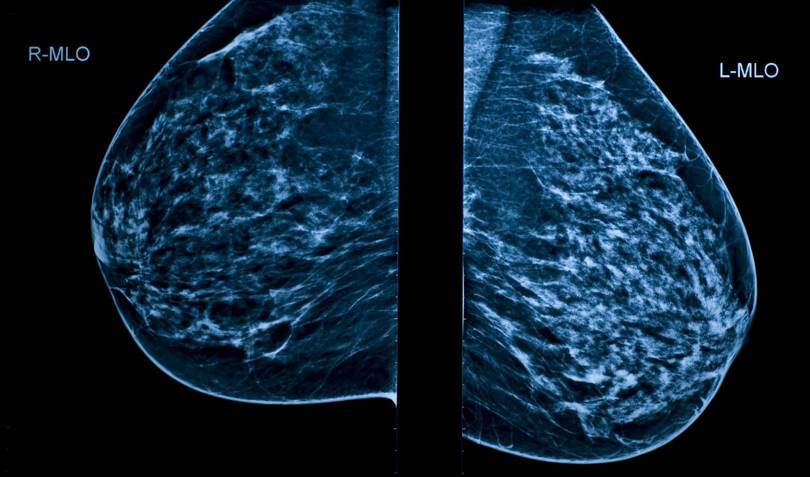

Так, например, в медицине обработка изображений применяется для более точной постановки диагнозов. Исследователи института в Хьюстоне разработали программу , способную прогнозировать развитие рака груди. Для этого необходимы данные с маммограмм и медицинские истории пациенток. Подобные технологии используются и в России — российская платформа Botkin.AI позволяет выявлять онкологические заболевания легких благодаря анализу медицинских изображений с помощью технологий искусственного интеллекта.